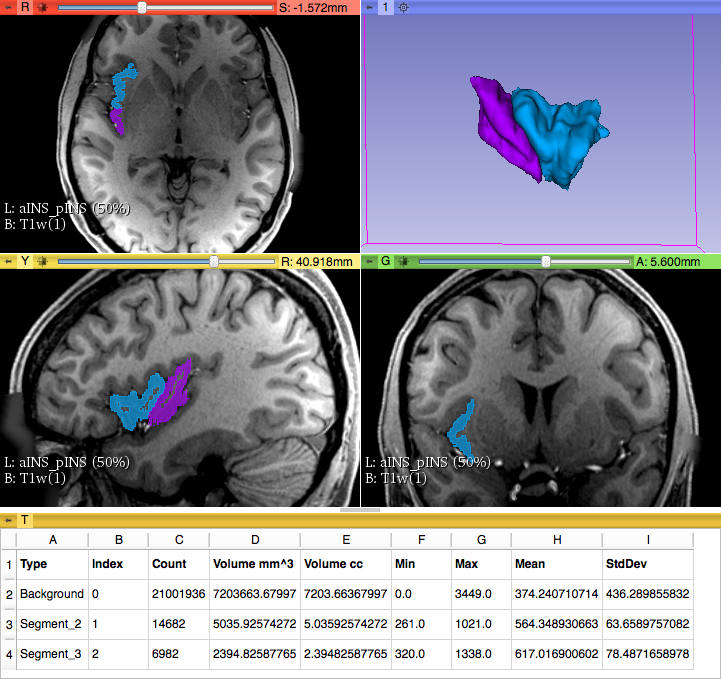

6) We selected the third segment added before.

5) On the 3D model of the parcellated Insula (in 3D view), we then used the ‘Scissors’ tool using the Central sulcus as the guideline to separate the aINS from the pINS. Subsequently, we checked the precision of the border of aINS and pINS as informed by the central sulcus.

6) To calculate the volumes of and and pINS, we first exported the segments converting them in labels using in Segment Editor the ‘Segmentations’ function.

7) Finally, we used the ‘Quantification’ module, ‘Label Statistics’ to obtain volumetric measures of each label (aINS, pINS).

The entire procedure lasted 6 hours.

Parcellation of aINS and pINS - Volumetric measures

3D model of the "Insula of Reil"